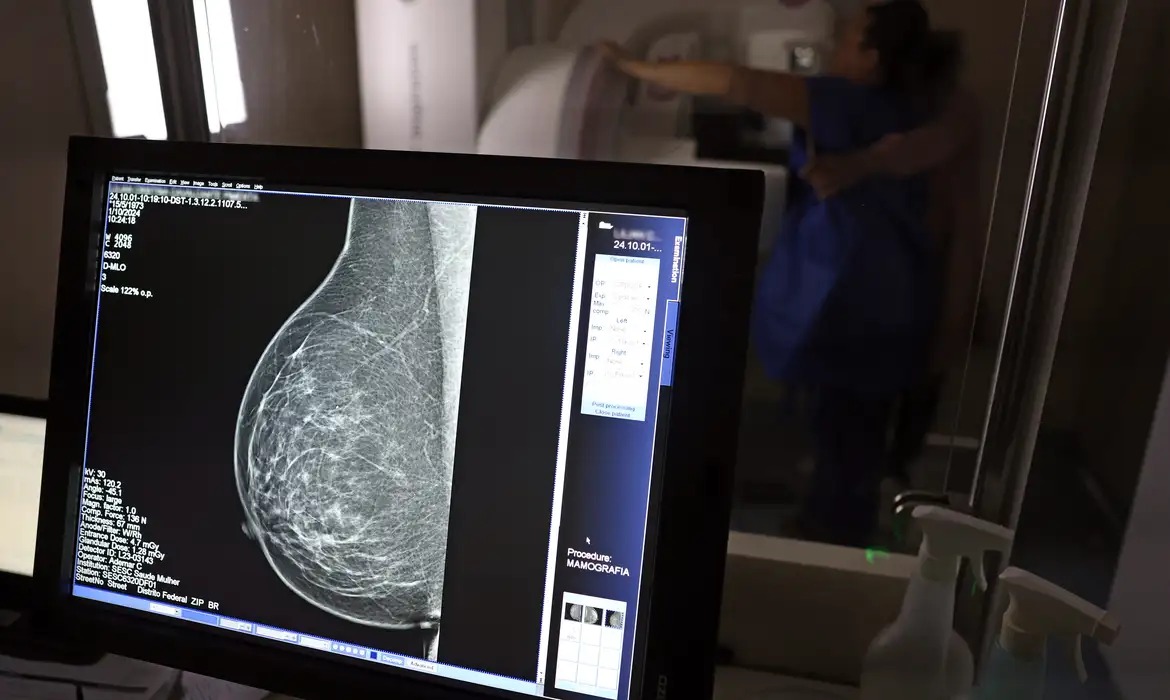

No Outubro Rosa, Inca estimou 73.610 novos casos este ano no país/Foto: José Cruz/Agência Brasil

No Outubro Rosa, Inca estimou 73.610 novos casos este ano no país (Foto: José Cruz/Agência Brasil)

No Outubro Rosa, o Instituto Nacional de Câncer (Inca) estimou 73.610 novos casos este ano no país. É o câncer que mais mata mulheres no Brasil. As mulheres em tratamento pela doença têm o direito de receber o auxílio-doença ou o benefício de prestação continuada.